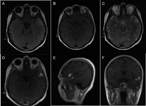

Anaplasic astrocytoma with exophytic growth in Sylvian fissure in a pediatric patient: a case report

José Raúl Guerra-Mora and others

Journal of Surgical Case Reports, Volume 2018, Issue 4, April 2018, rjy079, https://doi.org/10.1093/jscr/rjy079